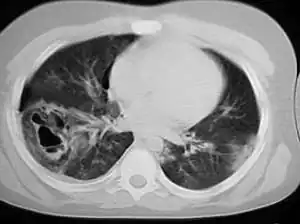

| A chest CT scan revealing pulmonary contusions, pneumothorax, and pseudocysts | |